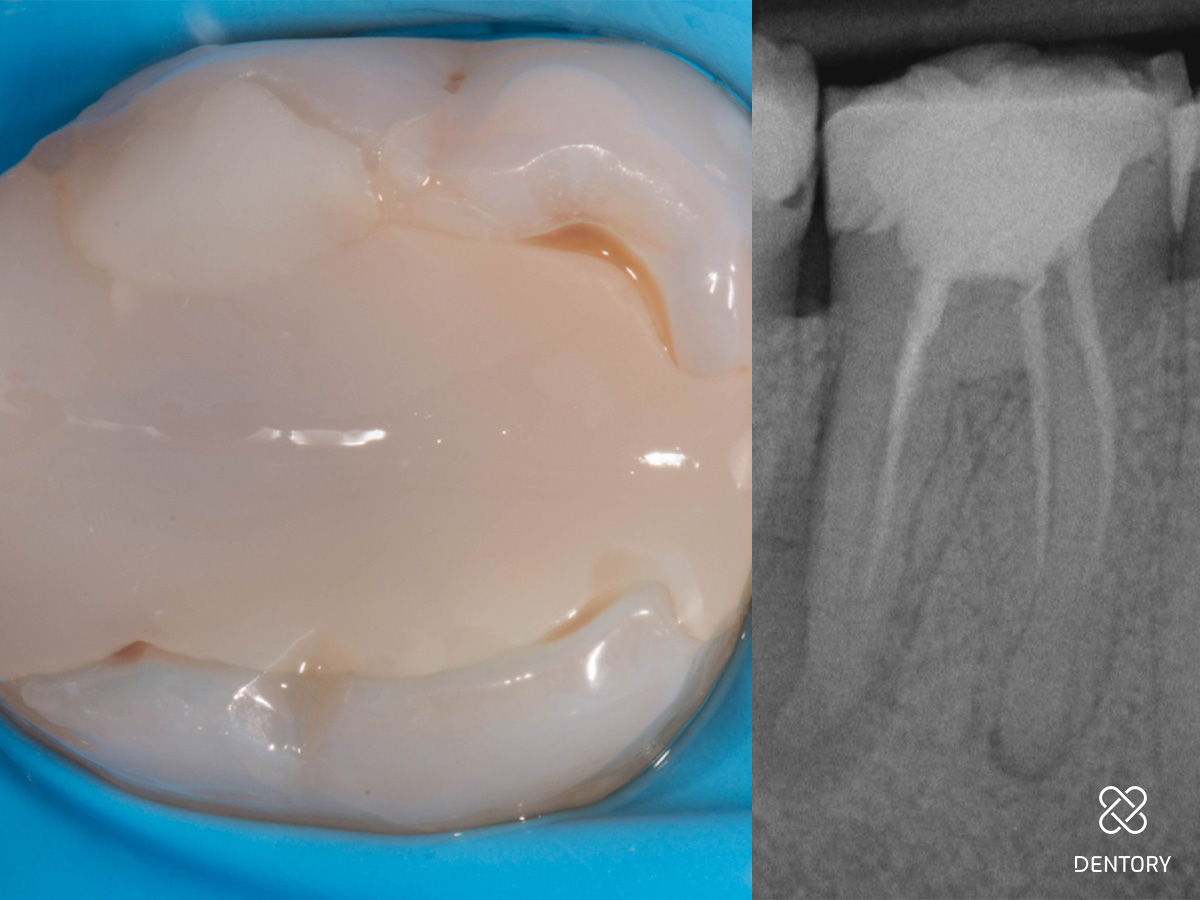

Abbildung 14

Wurzelfüllung-Kontrollaufnahme und Okklusionskontrolle.